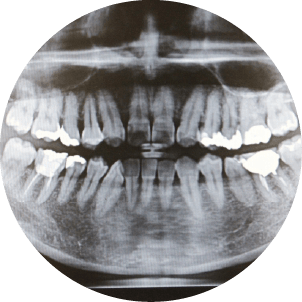

矯正治療を希望される方に対して、精密検査を実施しています。

精密検査は、患者様の歯並びや噛み合わせの問題をより詳細に把握し、最適な治療計画を立てるために不可欠なステップです。